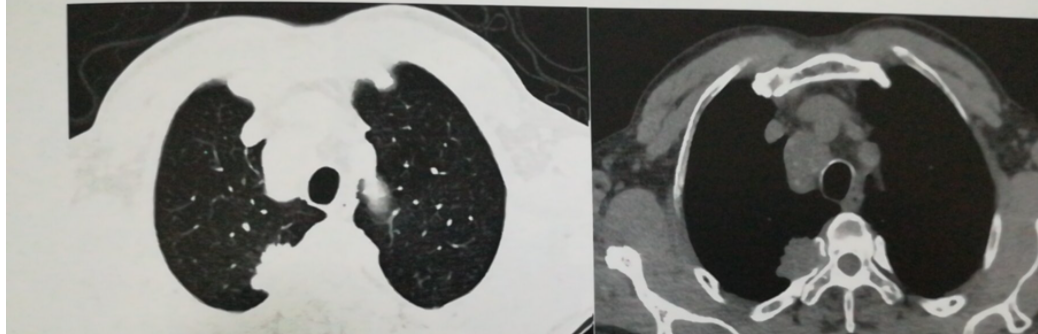

呼吸系统。CT检查在呼吸系统方面的检查那可谓是真频繁,尤其是在气管和支气管疾病、肺先天性疾病、肺炎、肺结核、肺真菌病以及肺肿瘤,像肺癌的筛查,首选就是低剂量螺旋CT.

(右上肺肺癌)